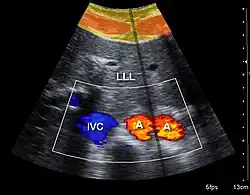

Both abdominal and endoanal ultrasound are frequently used in gastroenterology and colorectal surgery. In abdominal sonography, the major organs of the abdomen such as the pancreas, aorta, inferior vena cava, liver, gall bladder, bile ducts, kidneys, and spleen may be imaged. However, sound waves may be blocked by gas in the bowel and attenuated to differing degrees by fat, sometimes limiting diagnostic capabilities. The appendix can sometimes be seen when inflamed (e.g.: appendicitis) and ultrasound is the initial imaging choice, avoiding radiation if possible, although it frequently needs to be followed by other imaging methods such as CT. Endoanal ultrasound is used particularly in the investigation of anorectal symptoms such as fecal incontinence or obstructed defecation. It images the immediate perianal anatomy and is able to detect occult defects such as tearing of the anal sphincter.

Doppler ultrasonography employs the Doppler effect to assess whether structures (usually blood)[58][61] are moving towards or away from the probe, and their relative velocity. By calculating the frequency shift of a particular sample volume, flow in an artery or a jet of blood flow over a heart valve, its speed and direction can be determined and visualized, as an example. Color Doppler is the measurement of velocity by color scale. Color Doppler images are generally combined with gray scale (B-mode) images to display duplex ultrasonography images.[62] Uses include: